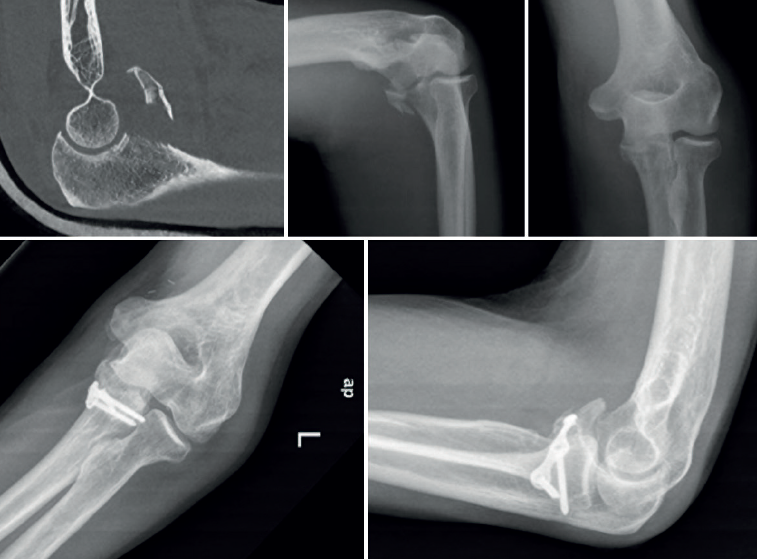

La apófisis coronoides es un factor clave en la estabilidad del codo, ya que contribuye significativamente a la estabilidad anterior y posterolateral. La reparación de la fractura debe ser prioritaria, después de la reducción de la luxación y la evaluación de la cabeza radial. Para guiar la intervención quirúrgica, utilizamos la clasificación de O’Driscoll(17)(Figura 6):

- Tipo I: fractura del vértice de la apófisis coronoides. Dentro de este tipo, se subclasfican en tipo I (< 2 mm) y tipo II (> 2 mm). Como referencia anatómica de importancia, la inserción de la cápsula anterior se sitúa 6,4 mm distal a la punta de la coronoides en promedio(18). Todavía existe controversia sobre la fijación o no de un pequeño fragmento de coronoides (tipo I). Terada N, et al.(19) abogan por una fijación sistemática para conseguir una reducción anatómica y restaurar la estabilidad. En un trabajo previo(20), Regan y Morrey no están a favor de una fijación quirúrgica en este tipo de lesiones. En nuestra experiencia, si es posible, se intenta una reparación para conseguir una reducción anatómica y una restauración de la columna anterior. La reparación se realiza bien con tornillos canulados interfragmentarios o con anclajes transóseos de sutura en aquellos fragmentos de menor tamaño(21,22). La capsulodesis de la cápsula anterior podría ser una alternativa en aquellos casos de inestabilidad posterior persistente o en aquellas fracturas pequeñas de coronoides irreparables que asocian una rotura anterior de la cápsula(23)(Figura 7).

- Tipo II: fractura anteromedial de la apófisis coronoides. Puede o no incluir el vértice la apófisis (II-2) o el tubérculo sublime (II-3) donde se inserta la banda anterior del LCM. Estas fracturas comprometen la estabilidad del codo debido a la pérdida de la función estabilizadora de la parte anteromedial de la apófisis. Es necesario fijar estas fracturas con tornillos o una placa anatómica conformada para coronoides(24,25)(Figura 7).

- Tipo III: fracturas que afectan más del 50% de la base de la apófisis coronoides. Las fracturas transolecraneanas que afectan a la base de la coronoides se clasificarían como un III-2. Generalmente, requieren una placa de bloqueo anatómica para estabilizar los fragmentos óseos o placas dobles si hay conminución grave(26)(Figura 8).